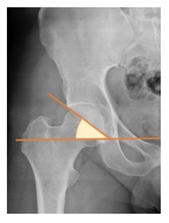

| Sharp angle | the angle between a line passing from the superior to the inferior acetabular rim and the horizontal plane | <42° | ![]() |